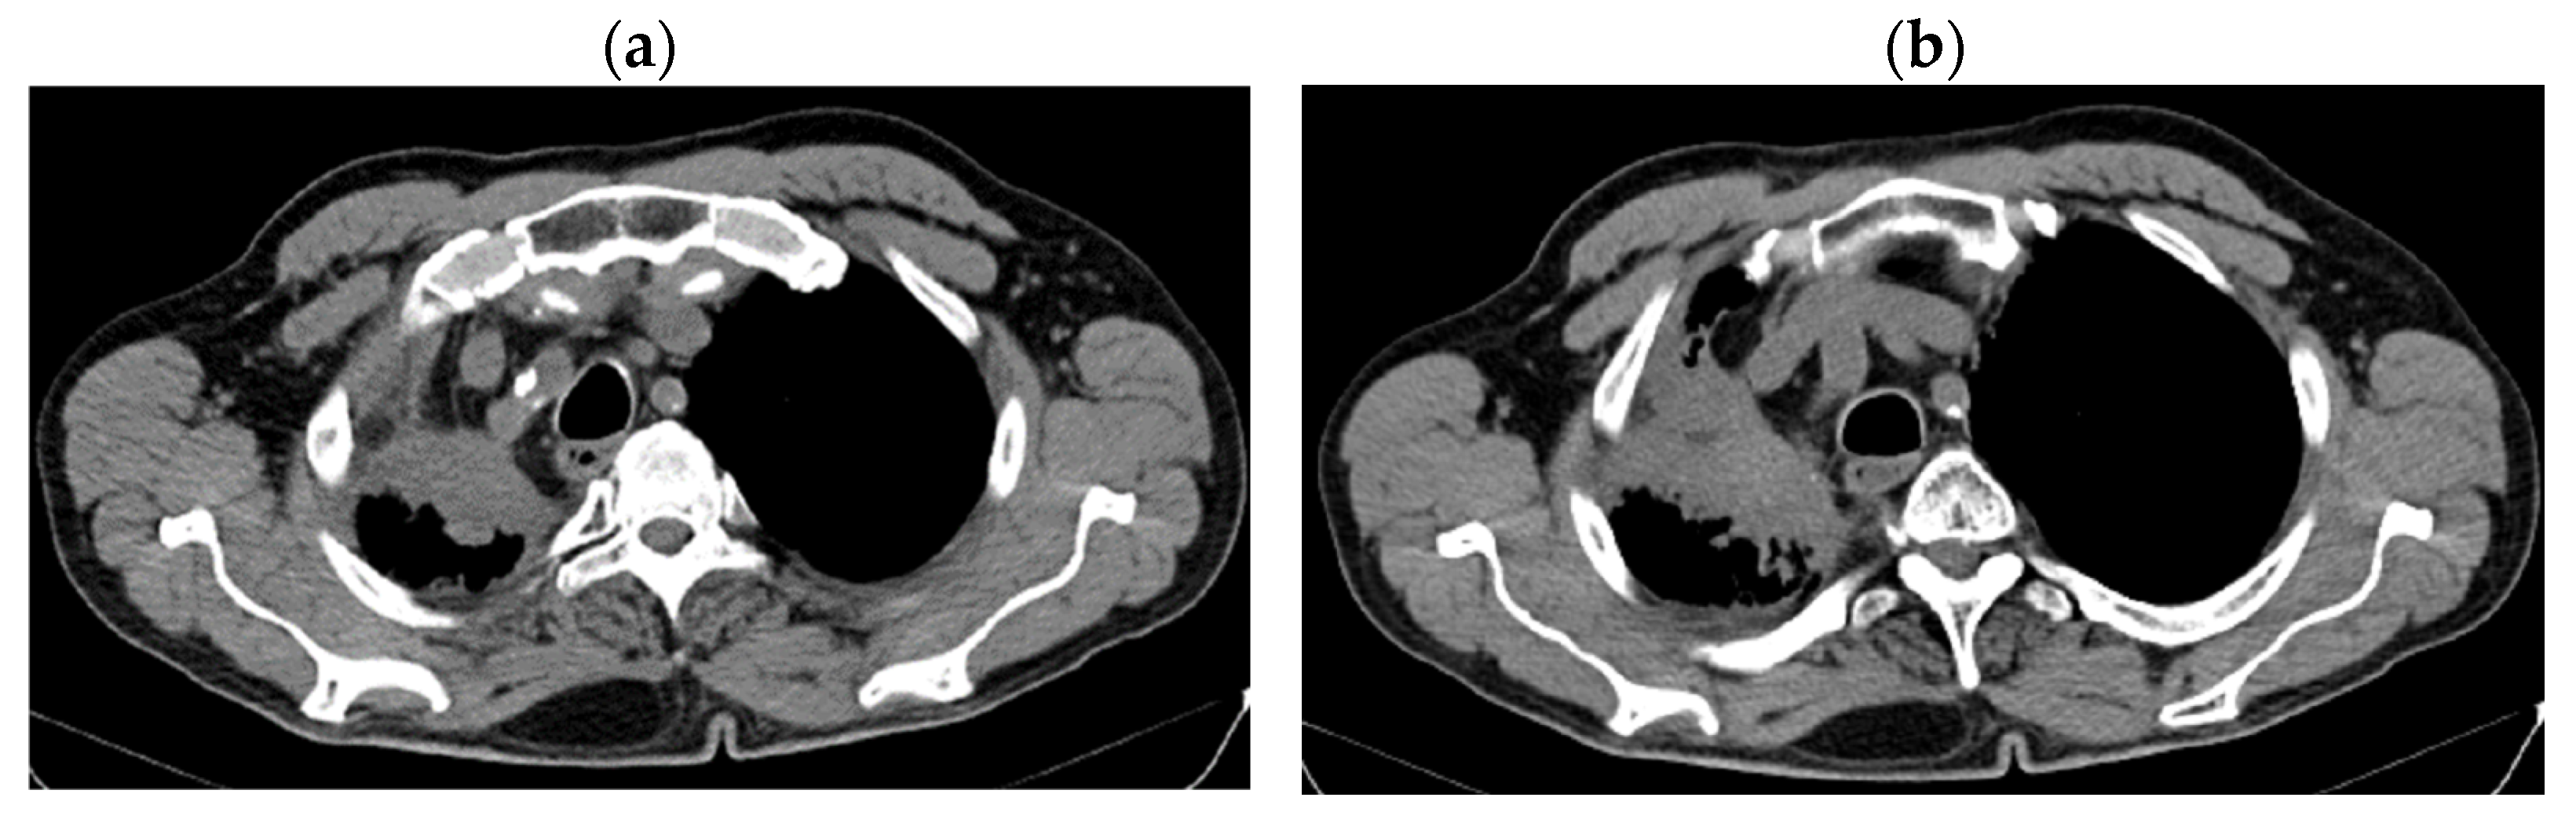

2. Case Presentation

2.2. Monitoring 2022: Oncological Commission 1910/16.08.2022

2.3. Oncological Committee 07/25/2023 Recommended

- Consider rescue re-irradiation (SBRT), taking into account the current primary tumor dimensions of 24 × 34.2 mm on PET CT from 06/2023 and also the total dose previously administered (08–09/2020), the previously applied fractionation, the time between the two irradiations, the cellular repair time and the dose constraints for the organs at risk.